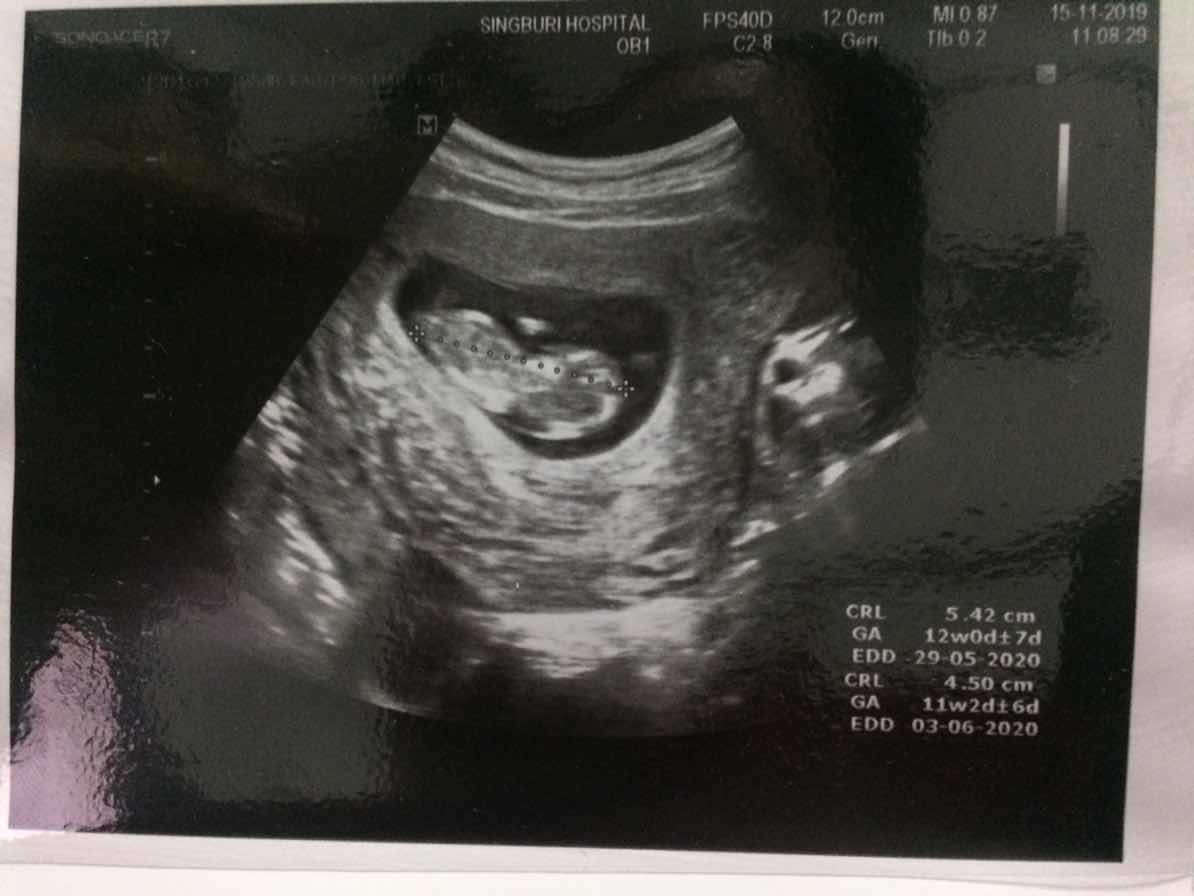

ปัจจุบันอายุครรภ์ 12 วีค 3 วัน แล้วแต่เมื่อช่วงอายุครรภ์ 11 วีค 5 วันหมอแจ้งว่าไม่เจอหัวใจน้องอยากขอดูใบซาวด์แม่ ๆ หน่อยได้ไหมคะ เป็นอย่างไรกันบ้าง

ตอน 13 สัปดาห์ค่ะ

ประมาณนี้ค่ะ

ตอน 11 วีคค่ะ

13 วีค ค่ะ.